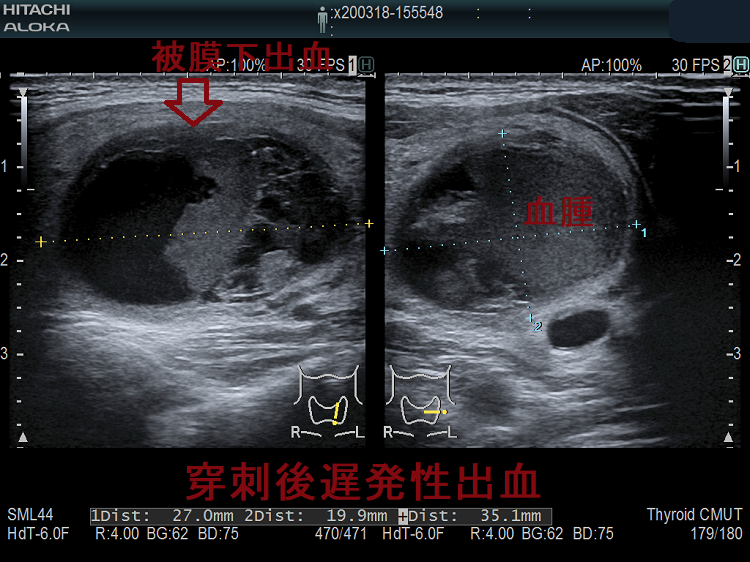

特に、のう胞性腫瘍(嚢胞性腫瘍)の排液を行う場合、粘稠な液が多いため太い針(21G)を使用します(輸血用の18G針を使う施設もありました)。当然、刺し口も大きくなるため、出血の危険が増します[のう胞内出血(嚢胞内出血)]。また、穿刺当日は何もなくても、塞がった刺し口が完全に固まるまでは脆弱なため、無理な力が掛かると、穿刺2週間後でも出血をおこします(穿刺後遅発性出血)。

甲状腺穿刺細胞診後の巨大血腫・活動性出血

(報告例)甲状腺穿刺細胞診から3時間後、重度の呼吸困難をきたし、気管内挿管。造影CTで気管を圧排する巨大血腫(上の写真左)と、活動性出血を示唆する造影剤の漏れ(Extravasation)(上の写真右)を確認。